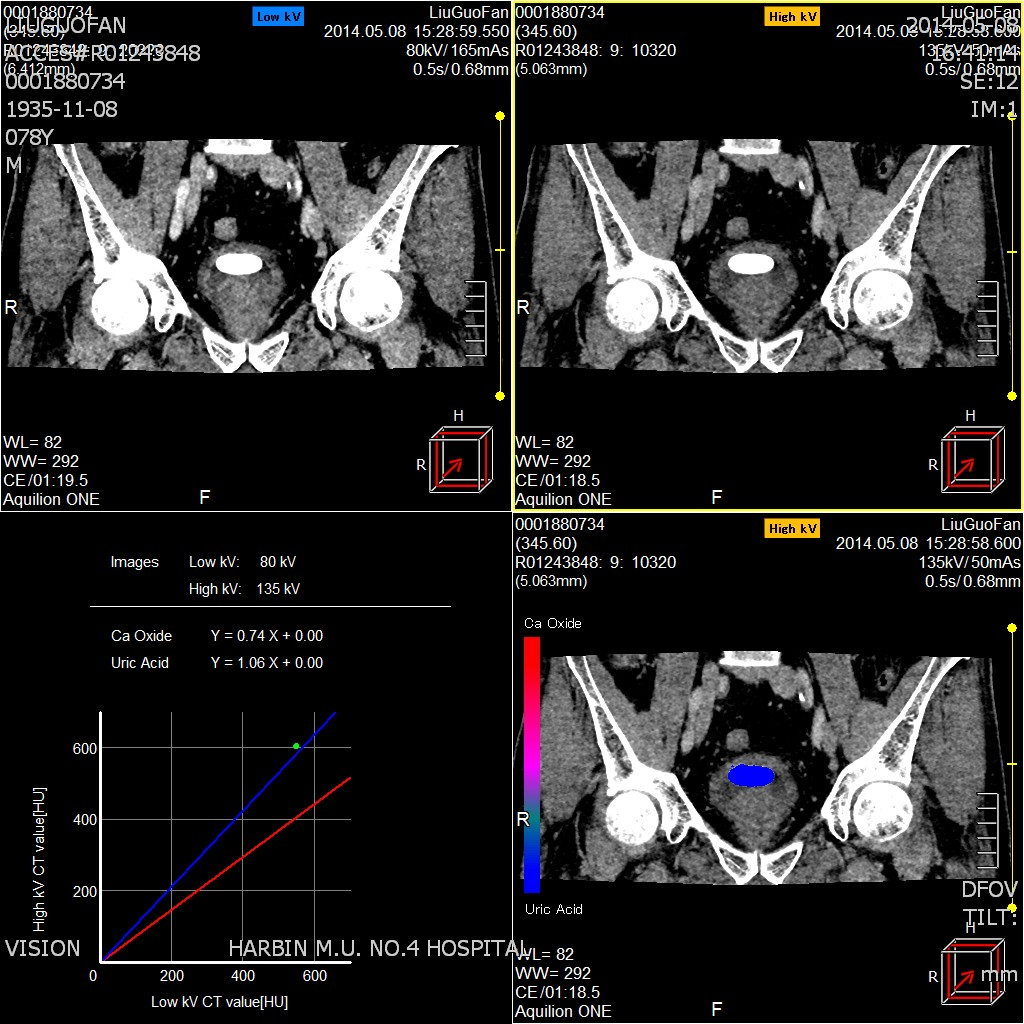

二、能谱痛风分析

用于痛风病的早期发现和诊断,能够明确显示尿酸盐结晶或结石 ,可以发现刚刚形成的尿酸盐结晶微粒,得到尿酸盐结晶数量、大小、位置等全面信息 ,显示尿酸盐结晶、结石对周围关节、软组织有无影响,有无骨质破坏。